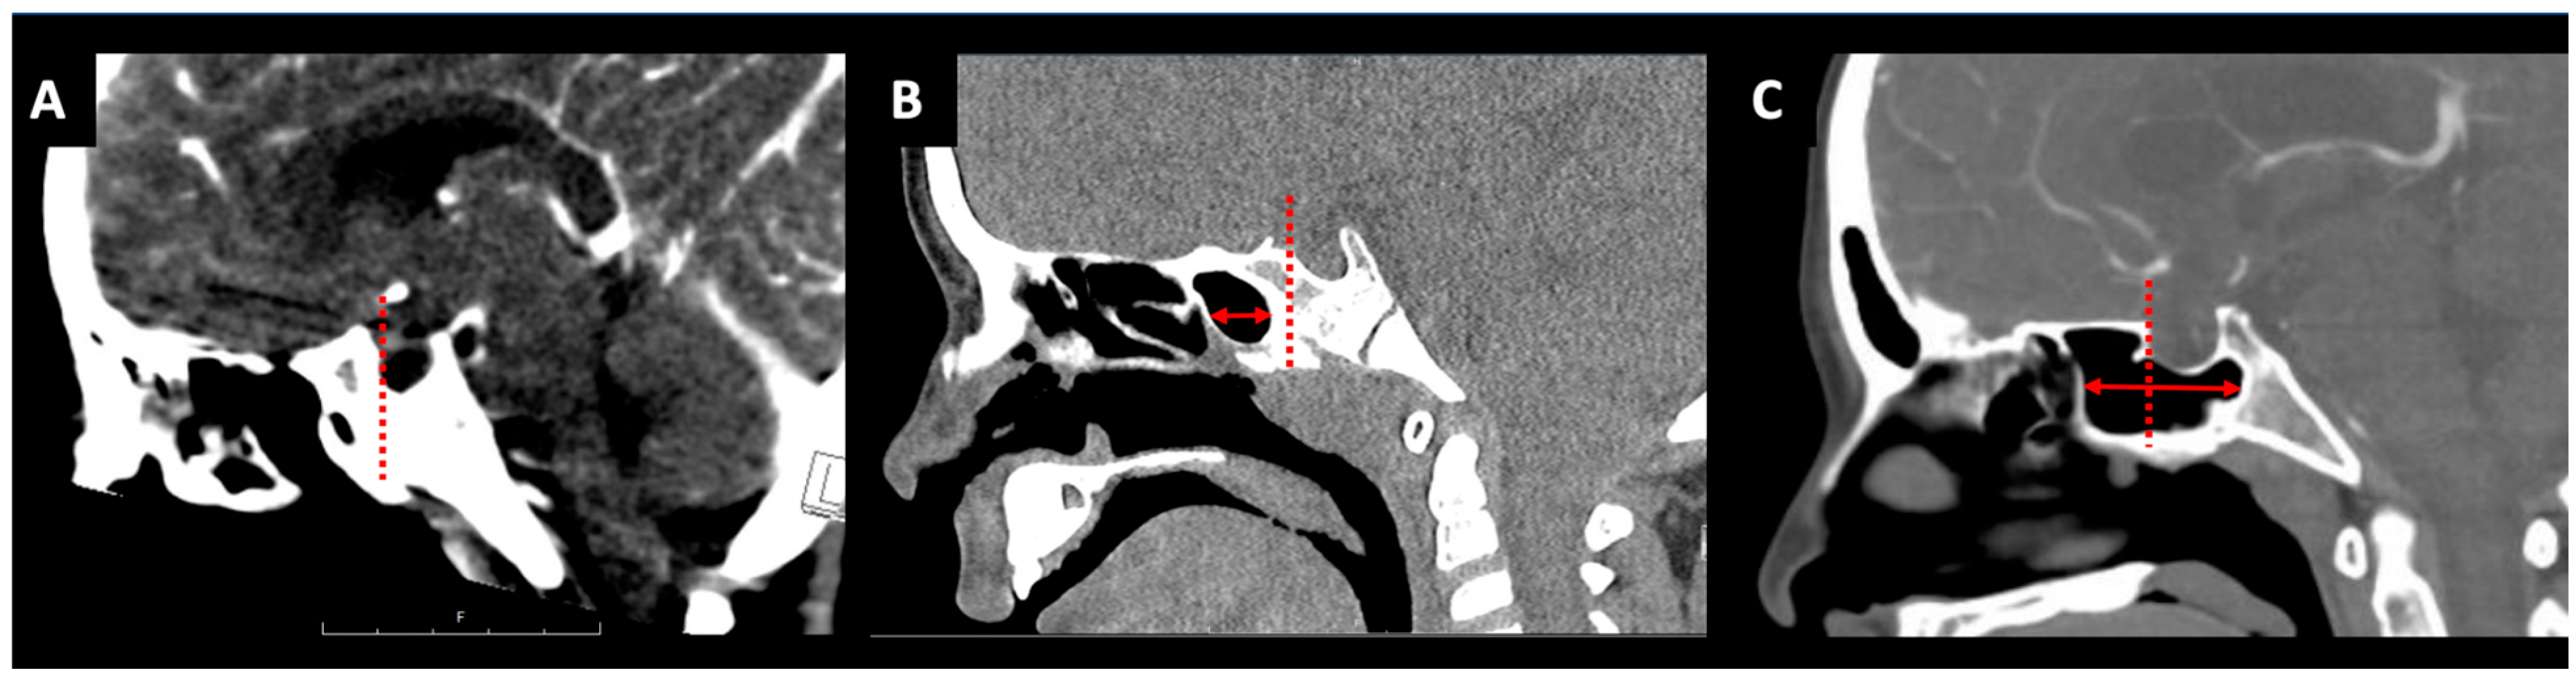

2.1. Nasal and Pyriform Apertures

2.2. Sphenoid Sinus Pneumatization

2.3. Intercarotid Distance